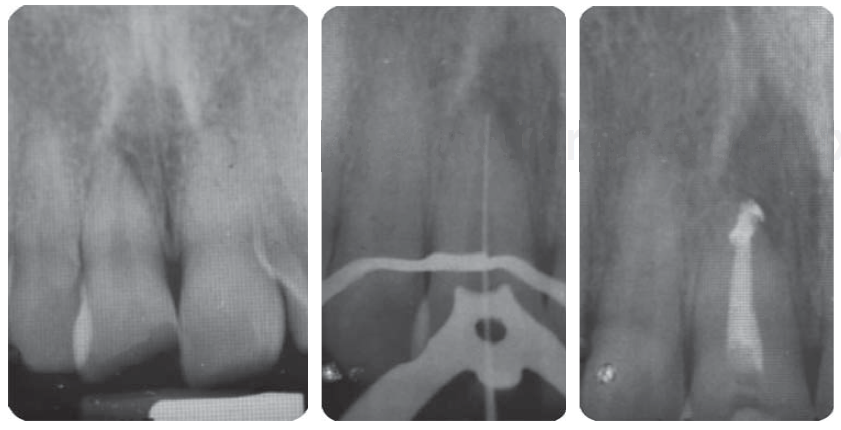

Tratamiento de sistema de conductos

Cicatrizada la cirugía de alargamiento de corona, se contó con mayor estructura dental, lo cual facilita y asegura el aislamiento para conformar los conductos con instrumentos manuales (K-FlexoFile, Dentsply Maillefer) y fuerzas balanceadas (Figura 11), protocolo de irrigación con hipoclorito de sodio al 5.25% y obturación vertical con técnica de Schilder usando cemento endodóntico MTA Fillapex (Angelus ®).16,17,18

Reconstrucción con postes de fibra de vidrio

Con aislamiento absoluto, se realiza la desobturación con instrumentos de compactación vertical de Schilder, se toman radiografías control de desobturación y ajuste de los postes de fibra de vidrio RelyXTM Fiber Post® 1.3Ø amarillo (3M ESPE). Se graba con ácido fosfórico al 37% por 20 seg, se lava el conducto con espray de agua y se seca con puntas de papel; el cementado del endoposte de fibra de vidrio y la reconstrucción coronal se realiza con el sistema del cemento resinoso Rebilda DC® (VOCO) (Figura 12), se toma radiografía control de la cementación.19,20 Cuidando exhaustivamente el protocolo de adhesión, una vez reconstruidos y preparados, se planifica cementar con ionómero de vidrio los provisionales de larga duración de Telio Lab (Ivoclar Vivadent), para mayor comodidad y estética del paciente (Figura 13).21

En la exploración clínica extra e intraoral sólo se observa la fractura dental (Figura 26), en la radiografía se observa el tratamiento de sistema de conductos (Figura 27).

Reconstrucción con poste de fibra de vidrio

Desobturación con instrumentos de compactación vertical de Schilder, tratando de sellar mejor al momento de termoplastificar la gutapercha, se toma radiografía control de desobturación, observando que el Drill del sistema a utilizar queda con espacios (Figura 29 A), se ajuste del poste de fibra de vidrio FRC Postec ® Plus tamaño 3, de la casa comercial Ivoclar Vivadent, cuyo diámetro coronal es de 2 mm y el apical de 1 mm (Figura 29 B). Se corta el poste de fibra de vidrio en una intensión con pieza de alta velocidad, fresa de diamante grano grueso y abundante irrigación, luego se graba, se lava, se seca el conducto y se cementa el endoposte de fibra de vidrio con la parte coronal del mismo hacia apical del conducto para de esta forma ser más congruentes con el diámetro de un diente joven y el excedente apical del poste se introduce como poste complementario en coronal del conducto, la cementación y reconstrucción coronal se realizó con el sistema del cemento resinoso Rebilda DC ® (VOCO), finalmente se toma una radiografía control de cementación (Figura 29 C).

Figura 29 A) Desobturación. B) Prueba del poste de fibra de vidrio. C) Cementación del poste de fibra de vidrio.